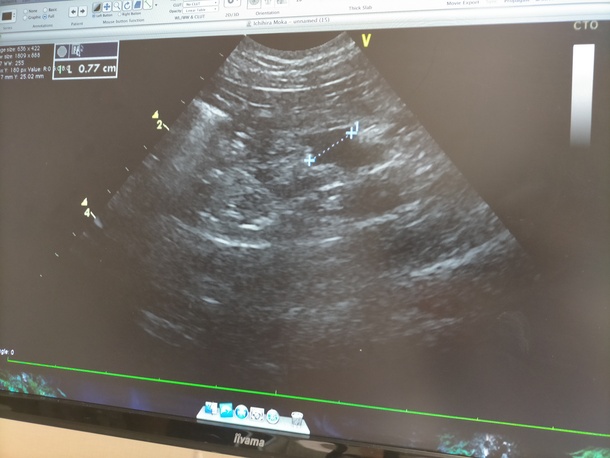

7mmの腫瘍と治療方針

今日も通院日でした!!

血液検査やけに長いなぁと思ったら、丁寧にエコー検査をして下さっていたようで、

その結果ほぼ全て消えたと思っていた腫瘍が……まだいました😭

サイズは7mmほど。

モカは血液の癌なので、体中のどこにでも

出来る可能性があり、また、リンパ節は物凄い数があるので、見つけるのが難しく、同じ箇所かどうかの断定も難しいようで、

今日見つかったのは、恐らく突然出来たわけじゃなく、前回見当たらなかっただけで、元々あったものじゃないかとの事でした😣

結局、やはり寛解ではありませんでしたが、増殖したり緊急で健康を害するような状態ではないとのことで、2週間に1回に切り替えていきましょう!!と😭